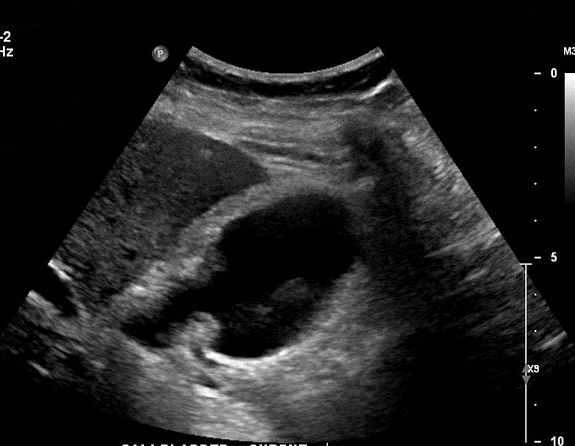

Aspect echographique d'une

adenocarcinoma vesiculaire : Image une masse

hyperechogene heterogene a bord irregulier

intraluminal avec epaissisement de la paroi en se voyant tres nette . Image de gros calcul a

infundibulum de la vesicule biliaire ( cone

acoustique posterieure ) |